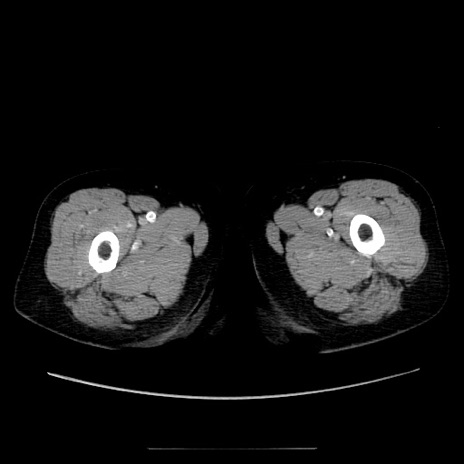

症例5(横断像)

【症例】70歳代女性

【主訴】お腹が張る

【現病歴】1週間くらい前から腹部膨満の自覚あり。昨日夜から増悪したため、本日救急外来受診。

【身体所見】意識清明、BT 36.5℃、BP 165/106mmHg、HR 80bpm、SpO2 98%、腹部:膨満、軟、自発痛・圧痛なし、触診にて不快感あり、腸蠕動音:減弱

【データ】WBC 12600、CRP 1.04